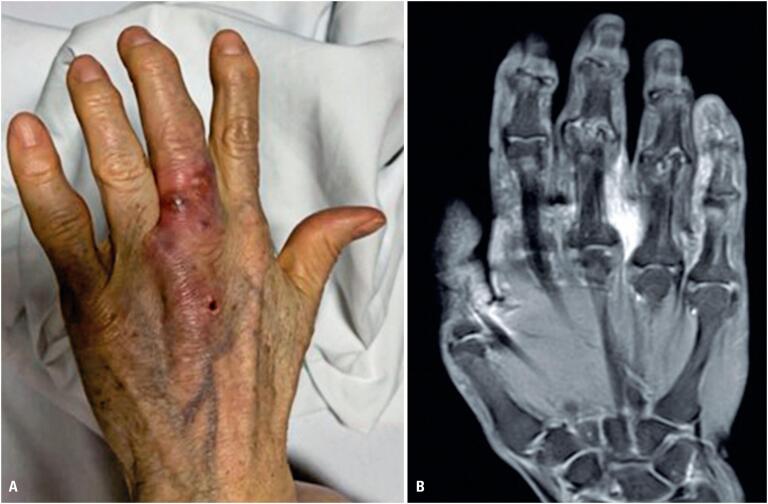

背景:真菌感染在近几十年来逐渐增加,发病率高,已成为一个公共卫生问题。骨关节真菌感染是由直接接种、连续感染传播或微生物的血源性播散引起的。毛丝虫病是一种类似酵母的担子菌,其中朝日毛丝虫病是最常见的致病菌。这篇文章描述了一个罕见的病例引起腱鞘炎的阿萨希毛磷虫在免疫功能正常的病人。伏立康唑治疗取得了良好的临床疗效。

Background: Fungal infections have become a public health problem owingdute to their progressive increase in recent decades and high morbidity rates. Fungal bone and joint infections result from direct inoculation, contiguous infection spread, or hematogenous seeding of organisms. Trichosporon spp. are yeast-like basidiomycetes, with Trichosporon asahii being the most common pathogenic species. This article describes a rare case of tenosynovitis caused by Trichosporon asahii in an immunocompetent patient. Treatment with voriconazole resulted in an excellent clinical response.